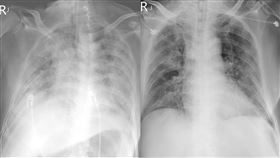

大白肺台商定序出爐!莊人祥揭高風險因子

北市聯醫胸腔科醫師蘇一峰,日前於1月7日於臉書上貼了...

2023/01/10 15:18

大白肺台商最新病況 醫:台灣醫護就是強

胸腔科醫師蘇一峰6日透露有位台商從中國返台後確診,拖...

2023/01/10 20:59